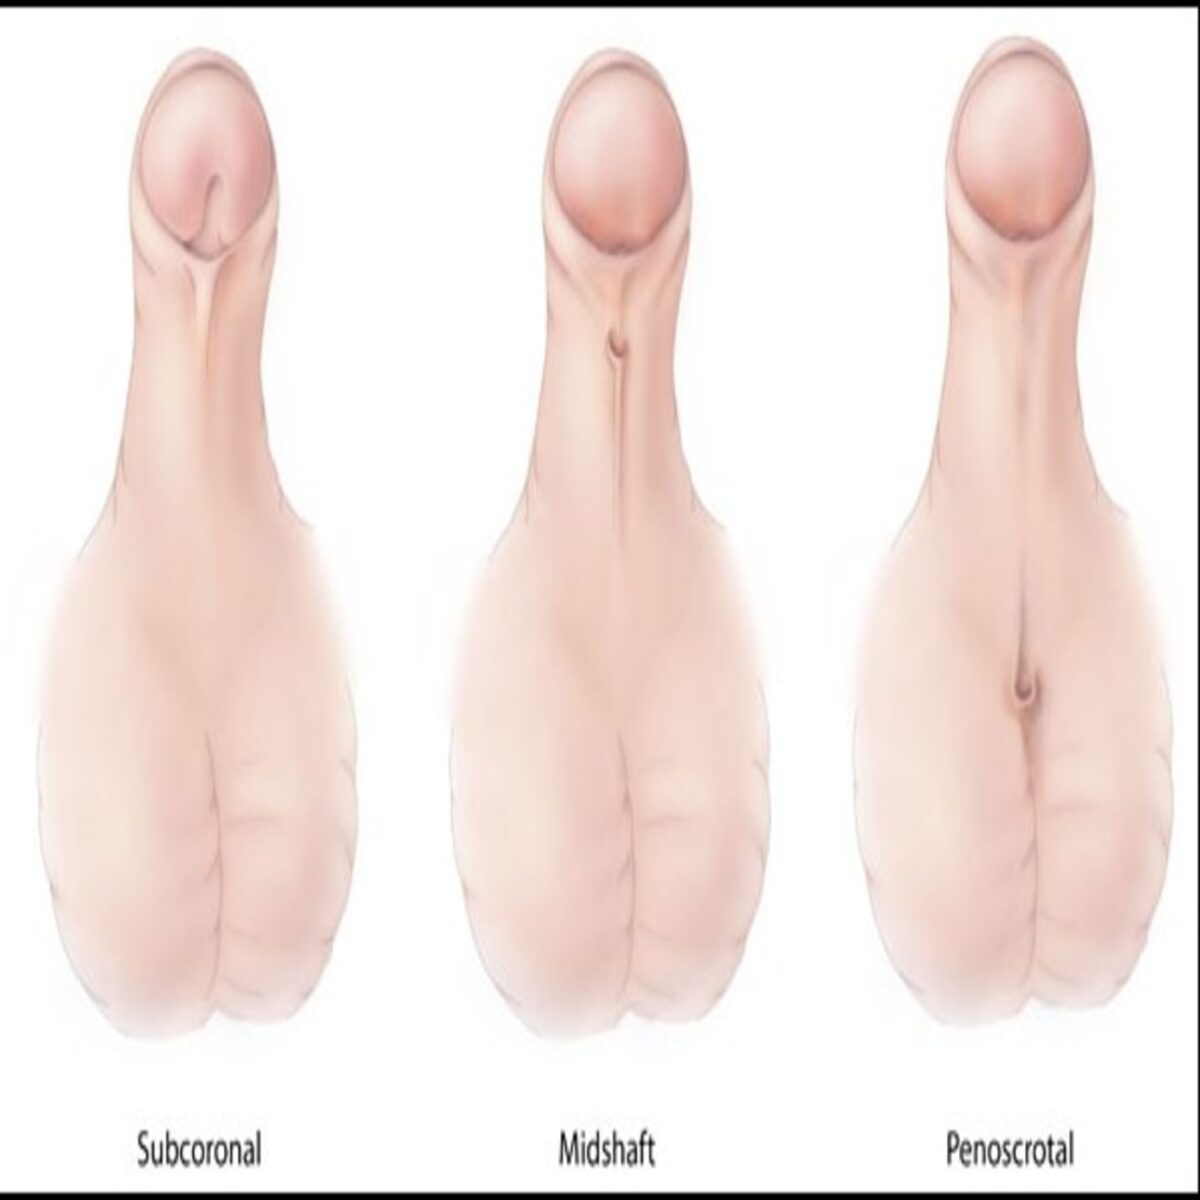

RECONSTRUCTIVE UROSUREGRIES

Professional medical services